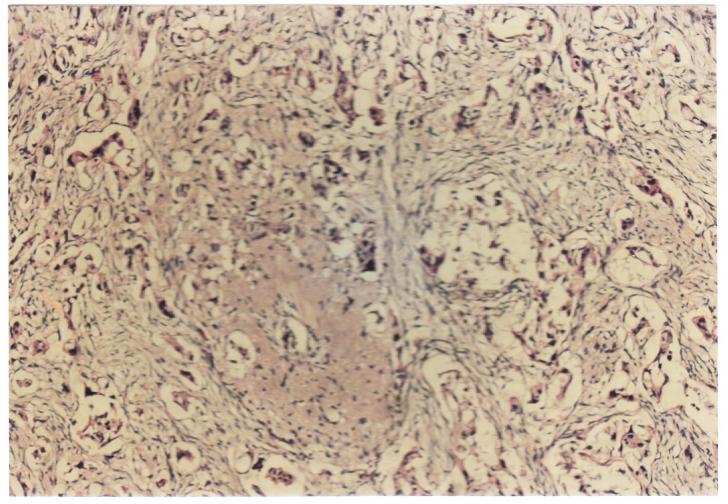

Criterii microscopice de diagnosticare a cancerului mamar

Criterii microscopice de diagnosticare a cancerului mamar      Investigarea citologica a proliferarii maligne se realizeaza prin tehnica citologiei exfoliative sau a citologiei prin punctie aspirativa cu ac fin. Prima tehnica se fo